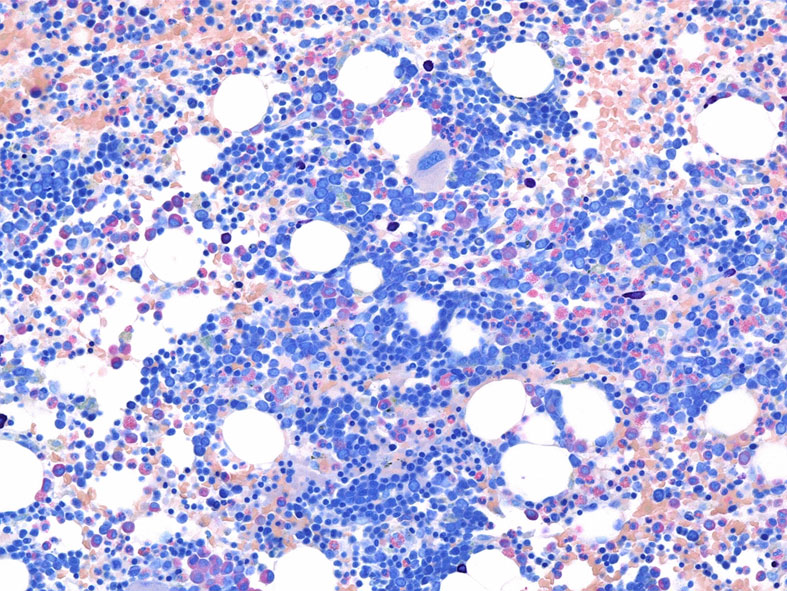

RARS(refractory anemia with ring sideroblasts:2016WHO分類ではMDS-RS)症例に見られたring sideroblastsです。(ベルリン青染色, x600)

Perlenkette (真珠の首飾り, ドイツ語)と呼ばれる青く染まった鉄顆粒が赤芽球の核周囲を取り巻くように認められます。

この青い顆粒はミトコンドリア内に貯留したフェリチン鉄ferritin ironです。

定義では, 5個以上の鉄顆粒が, 赤芽球の核周囲1/3以上を囲むものとされている。

骨髄塗抹標本と組織(clot section)の鉄染色(クリックで大きな画像がみられます) ring sideroblastは鉄顆粒が核周囲にまとわりつくように見える赤芽球として認められる。Hb合成の乏しい幼若な大型赤芽球では認められる鉄顆粒は少ない。